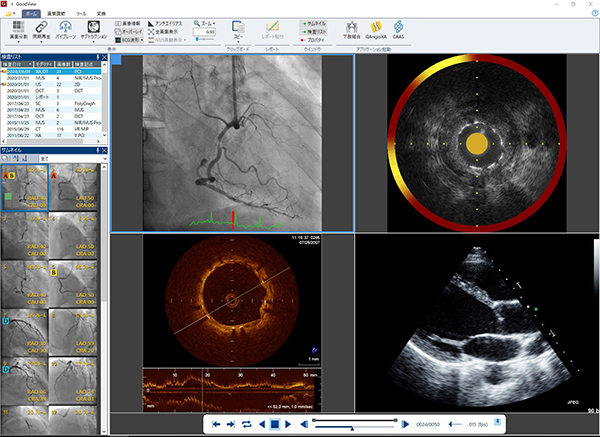

・DICOMビューワ「GoodView」シリーズ

GoodViewはシンプルなデザインかつ直感的な操作性を追求したDICOMビューワでありながら,IVUS画像の長軸比較表示,簡易計測機能やファイルフォーマット変換機能など医療現場で求められる多くの声をカタチにした多機能ビューワです。Goodnetの標準ビューワとしてだけでなく単体ソフトウェア「GoodViewPRO(Windows対応単体ソフトウェア)」としても提供しております。